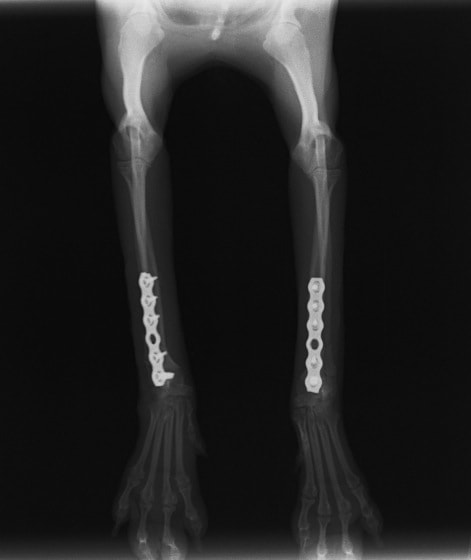

橈尺骨骨折 : 症例1 | 症例2 | 症例3 | 症例4 | 症例5 | 症例6 | 症例7

: 症例8 | 症例9 | 症例10 | 症例11 | 症例12 | 症例13 | 症例14

: 症例15 | 症例16 | 症例17 | 症例18 | 症例19 | 症例20 | 症例21

当院ではAdvanced Locking plate system(ALPS)と、Locking compression plate system(LCPS)という骨接合法で骨折症例の治療を行っています。

LCPは、スクリュー(ネジ)とプレート(金属の板)をロックする特殊な構造により骨折部位を固定する新しい世代のプレートシステムです。ひとつのホールでロッキングスクリューとスタンダードスクリューの使用を選択できるユニークな構造をしているため、骨折断端間の圧迫を目的とした従来型プレート固定法に加え、高い角度安定性を有するロッキングスクリューを用いた固定法の選択が可能です。従来のプレートシステムでは困難だった部分の骨折や癒合不全の症例に高い治療効果をもたらします。